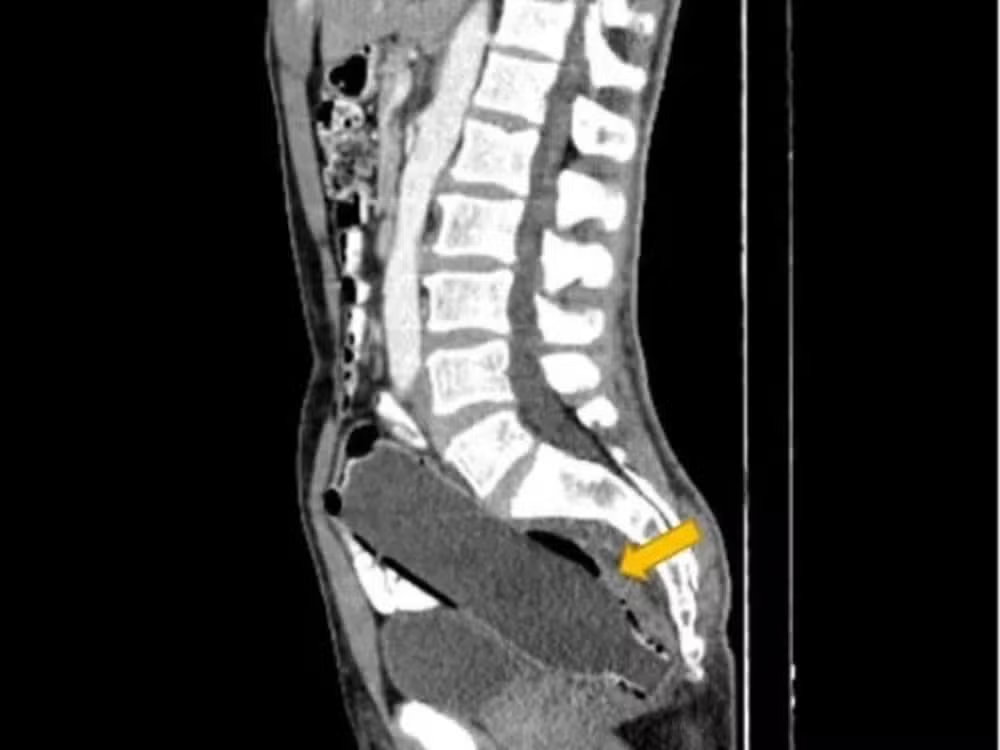

Daniella Hampton, de Nova Orleans (EUA), só descobriu em 2024 que seu DIU de cobre, colocado em 2009 e desaparecido misteriosamente, estava alojado em seu reto. A descoberta só ocorreu após um acidente de carro que exigiu um exame de raio-X. A cirurgia para remoção do dispositivo permitiu que Daniella engravidasse novamente três anos depois.